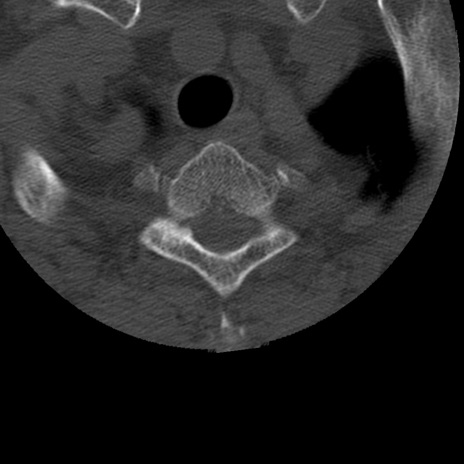

症例50 頚椎CT(横断像)

頚椎CT